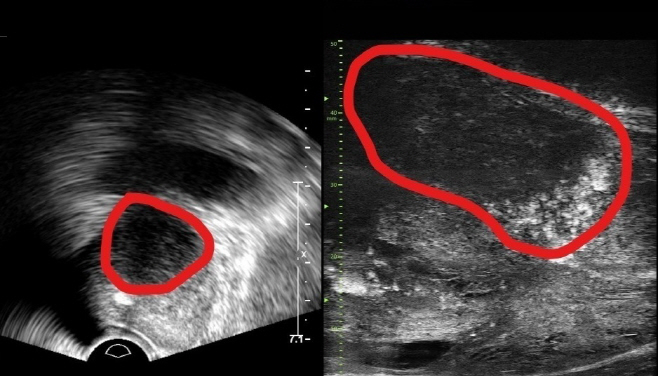

24일 분당서울대병원 비뇨의학과는 기존 초음파보다 3배 높은 해상도의 실시간 영상을 제공하는 마이크로 장비를 도입했다고 밝혔다. 전립선 종양을 정밀하게 평가하고 표적 조직검사를 수행할 수 있다는 게 병원 측 설명이다.

이 장비는 29MHz 마이크로 초음파를 활용해 전립선과 주변의 해부학적 구조를 선명하게 표시하고 미세한 병변을 식별한다. 또한 조직검사 바늘을 정확한 위치에 삽입할 수 있도록 유도한다.

장비는 전립선암 진단 가이드라인인 PRI-MUS 위험도 식별 시스템과 연계돼 있어 병변의 악성 가능성과 채취해야 할 조직 위치를 판별한다. PRI-MUS는 병변의 모양·크기를 자동으로 분석하고 악성도를 1~5단계(높을수록 위험)로 분류한다.

또한 자기공명영상(MRI)에서도 발견하기 어려운 전립선암을 찾아낼 수 있고 기존 경직장 초음파의 낮은 해상도 한계를 극복한다. 병원 측은 마이크로 초음파가 MRI 검사보다 환자의 신체적, 심리적, 경제적 부담을 줄일 수 있다고 설명했다.